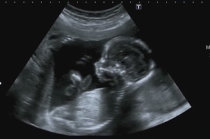

O ácido fólico atua na prevenção de anomalias congênitas42 no primeiro trimestre da gestação, tais como na prevenção primária da ocorrência de defeitos do fechamento do tubo neural31, que ocorre entre os dias 18 e 26 do período embrionário. Esses defeitos são, principalmente, anencefalia e espinha bífida9. O principal problema desta prevenção reside no fato de cerca de metade das gestações não serem planejadas e, assim, quando as mulheres descobrem que estão grávidas já é tarde para se fazer a suplementação11 com o ácido fólico e evitar tais anomalias.

De preferência, os comprimidos de ácido fólico devem ser tomados desde antes da concepção43, ou seja, quando a mulher ainda não engravidou. É importante também que as mulheres em idade reprodutiva tenham uma alimentação que contenha alimentos ricos em ácido fólico e que, assim que comecem a planejar uma gravidez8, comecem também a fazer uso de ácido fólico, de acordo com as orientações de seu médico.